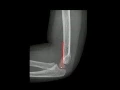

saudações a todos neste vídeo vamos conversar um pouco a respeito da avaliação da radiografia de cotovelo da criança no pronto socorro frequentemente essa avaliação fica sob a responsabilidade do clínico ou do cirurgião ou do pediatra que atende a criança com trauma de cotovelo e às vezes pode haver alguma dificuldade na interpretação do raio X em alguns casos vamos ver aqui alguns sinais que são extremamente úteis nessa avaliação algumas fraturas são muito óbvias como essa aqui né a fratura supracondilar completa deslocada e angulada do úmero né aqui o úmero aqui o rádio aqui a una já

isso aqui não é uma fratura aqui é um centro de dosificação normal do olécrano olécrano que ainda não se consolidou que ainda não fundiu aqui a placa de crescimento veja que há córtex dos dois lados dessa fenda Então não é fratura é placa de crescimento aqui duas radiografias de perfil de cotovelo de criança de duas pacientes diferentes nem sempre é fácil visualizar as alterações as duas T alterações que são diferentes em cada caso no final do vídeo H nós veremos como vai ficar um pouco mais fácil para visualizar e encontrar essas [Música] alterações primeiro alguma